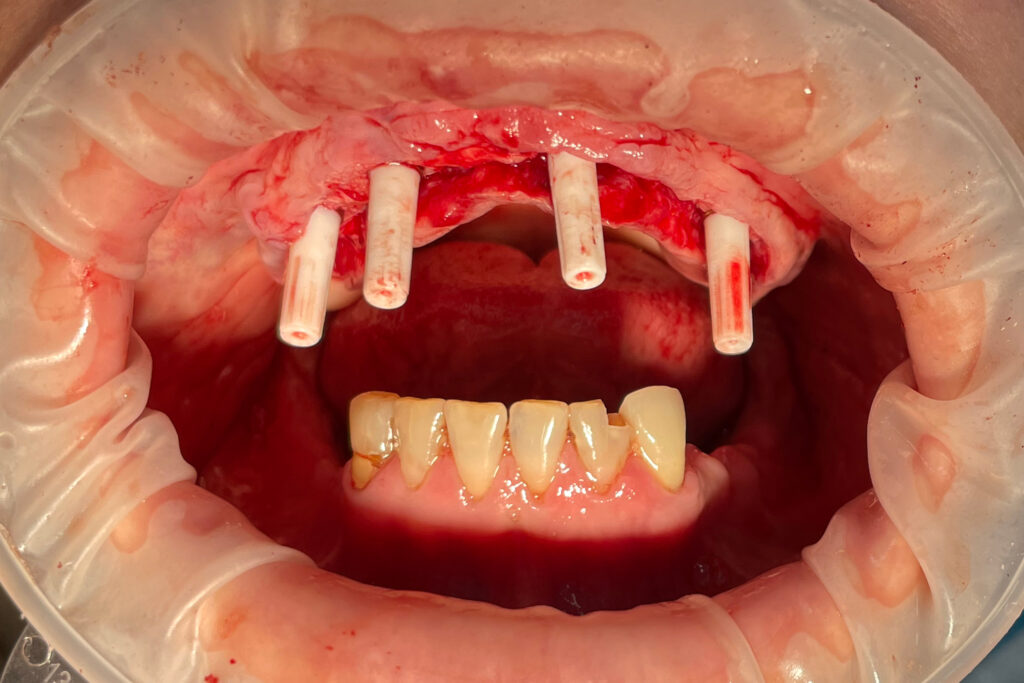

После проведенной консультации было принято решение о проведении комплексной имплантации по системе All-on-6.

После установки 6ти имплантантов Megagen AnyRidge были сняты оттиски для изготовления металлоакрилового протеза.

Процесс имплантации

Это фото может содержать тяжелый для восприятия контент